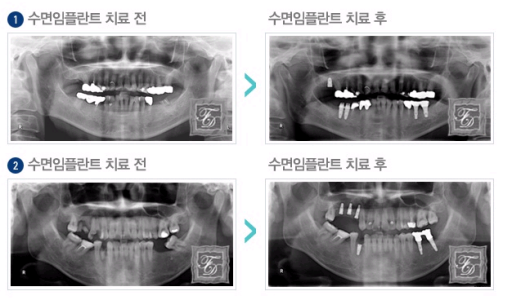

'수면치료'는 수면 마취를 통해 사랑니 발치, 충치치료, 신경치료, 보철치료, 스케일링, 임플란트까지 광범위하게 통증 없이 치료받을 수 있어 빠른 시간 안에 일상으로 정상복귀가 가능하다는 장점을 가지고 있다.

환자별 맞춤형 수면요법으로 편안하고 최적의 치료를 받을 수 있는 '수면치료'는 안전하고 편안한 수면 상태에서 통증 없이 치과를 할 수 있다.